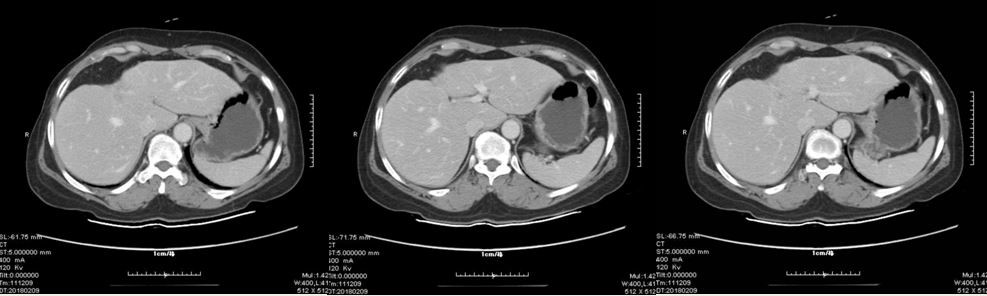

经与患者反复沟通,充分告知在乳腺癌中抗HER2治疗的必要性,患者同意采用曲妥珠单抗靶向治疗。于2017年11月起行卡培他滨联合曲妥珠单抗一线治疗至今。迄今为止定期复查,疾病处于稳定状态。

治疗后肝转移灶

患者于2014年2月行右乳腺癌改良根治术,术后确诊为:HER2阳性HR阴性乳腺癌。初始应予以AC-TH一线标准方案辅助化疗,但患者拒绝使用曲妥珠单抗,遂予以AC-T方案。2017年11月发现肝脏转移, 无病生存期(Disease-free  survival,DFS)44个月。复发后行卡培他滨(希罗达)联合曲妥珠单抗靶向抗HER2治疗,迄今为止多次评估,疗效评价完全缓解(complete remission,CR)。截止目前无进展生存期(progression-free survival, PFS)达13个月,未出现疾病进展。